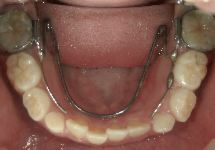

バイヘリックス(BH)

QHと同じく顎の骨幅を広げる効果があり、歯列の幅が広がります。ヘリカルループというワイヤーのくるくるが2つのため、QHよりも力は弱いですが、舌がある下顎には、かさばらないBHを使用します。